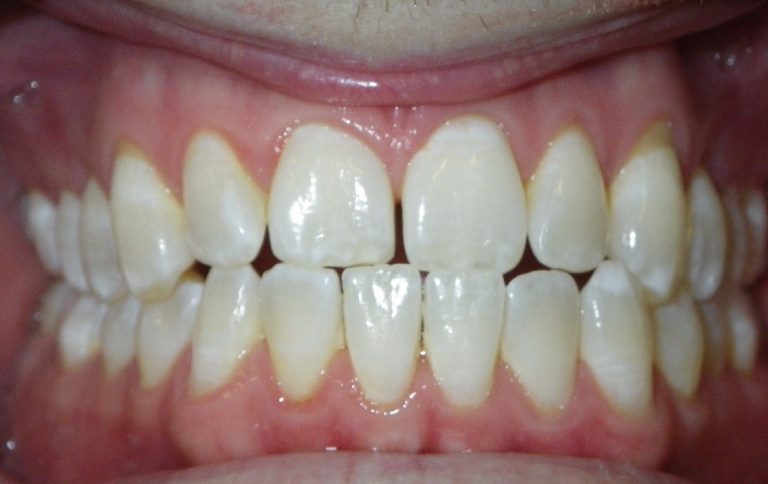

Classe III, articulé croisé antérieur, béance, espacement, diastème

État initial